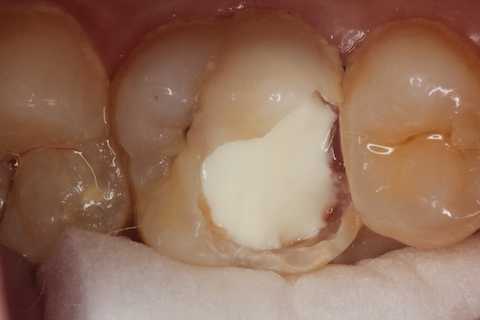

20代女性、左上6、自発痛+

確かに窩洞内はプラークまみれで、露髄しているので痛いのだろうな。。と思わせる。

でも、露髄していようが、感染歯髄だろうが、歯髄息肉だろうが関係ない。歯髄があるところまでα-TCPセメントで塞げば、痛みも止まるし、歯髄を保存できる。

次回はちゃんと充填して歯を作るからねーと言って仮封して帰ったが、痛みが止まったので、もうこれでいい!と勝手に判断して来ない。電話をかけても出ない。知らんわ、、

では時系列でどうぞ